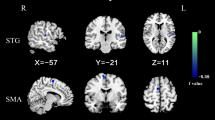

Compared to HCs, patients with OCD exhibited lower spFC and lpFC in the left precentral/postcentral gyrus (t = -5.57 and -5.43; P < 0.05, GRF corrected), and higher lpFC in the right thalamus/caudate, left thalamus, left inferior parietal lobule (IPL), and left cerebellum Crus I/VI (t = 4.59, 4.61, 4.41, and 5.93; P < 0.05, GRF corrected) (Table 2, Fig. 3, and Fig. 4). The VBM results showed no significant differences in the GMV values of the left precentral/postcentral gyrus, right thalamus/caudate, left thalamus, left IPL, and left cerebellum Crus I/VI between the two groups (TableS1 in the Supplementary Materials).

Brain regions with significant differences in spFC between patients with OCD and HCs. Blue denotes lower FC in patients. The color bar represents the T values from two-sample t tests. L = left; R = right; spFC = short-range positive functional connectivity; OCD = obsessive–compulsive disorder; HCs = healthy controls